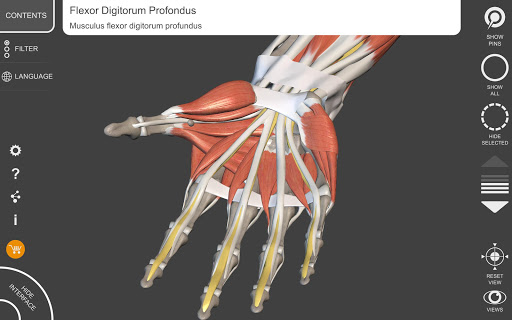

"Anatomy 3D Atlas" memungkinkan Anda mempelajari anatomi manusia dengan cara yang mudah dan interaktif.

Melalui antarmuka yang sederhana dan intuitif, Anda dapat mengamati setiap struktur anatomi dari sudut mana pun.

Model 3D anatomi sangat terperinci dan memiliki tekstur hingga resolusi 4k.

MODEL ANATOMI 3D

• Sistem muskuloskeletal

saraf • Sistem pernapasan • Sistem pencernaan • Sistem urogenital (pria dan wanita) • Sistem endokrin • Sistem limfatik • Sistem mata dan telinga FITUR • Antarmuka yang sederhana dan intuitif • Putar dan perbesar setiap model dalam ruang 3D • Opsi untuk menyembunyikan atau mengisolasi satu atau beberapa model yang dipilih • Filter untuk menyembunyikan atau menampilkan setiap sistem • Fungsi pencarian untuk menemukan setiap bagian anatomi dengan mudah • Fungsi penanda untuk menyimpan tampilan khusus • Rotasi cerdas yang menggerakkan pusat rotasi secara otomatis • Fungsi transparansi • Visualisasi otot melalui tingkat lapisan dari yang superfisial hingga yang terdalam • Dengan memilih model atau pin, istilah anatomi terkait akan muncul • Deskripsi otot: asal, • Tampilkan/ Sembunyikan antarmuka UI (sangat berguna dengan layar kecil) MULTIBAHASA • Istilah anatomi dan antarmuka pengguna tersedia dalam 11 bahasa: Latin, Inggris, Prancis, Jerman, Italia, Portugis, Turki, Rusia, Spanyol, Mandarin, Jepang, dan Korea • Istilah anatomi dapat ditampilkan dalam dua bahasa secara bersamaan PERSYARATAN SISTEM • Android 8.0 atau yang lebih baru, perangkat dengan RAM minimal 3GB Reversi